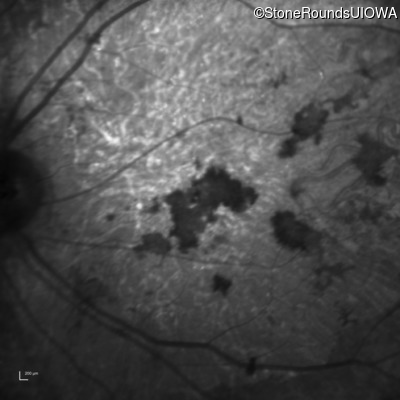

Infrared Fundus Photograph - Right - 20/150 sc

Exemplar